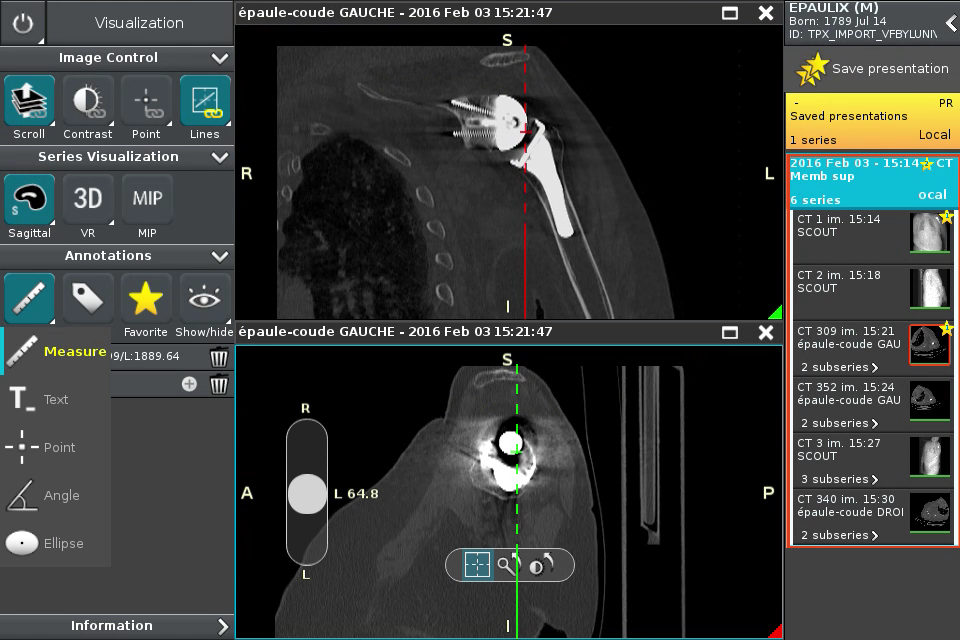

Anywhere Streaming is a DICOM visualization client that connects to Anywhere Server. It provide standard medical image navigation tools surch as : slicing, windowing, MPR, 3D VR, MIP, oblique ...

All standard medical image modalities are supported : MR, RX, CT, PET, NM, MG, US ...

Screenshots